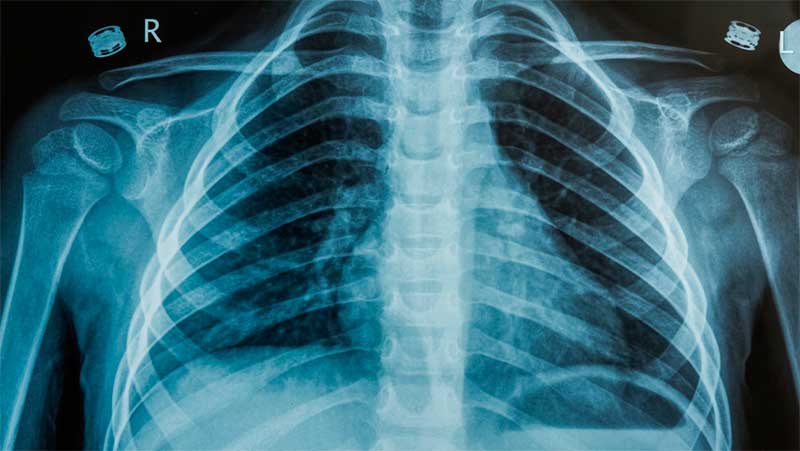

El hombre se había estado automedicando con medicinas de venta libre para la tos, pero, al no ver ninguna mejoría, a inicios de junio, acudió al Departamento de Cirugía Torácica del Hospital de Zhejiang para un chequeo. Una tomografía computarizada reveló una masa de aproximadamente un centímetro de largo dentro de su pulmón derecho, lo que hizo temer que tuviera un tumor maligno.

Zhu Xinhai, director del Departamento de Cirugía Torácica, explicó que el chile probablemente había llegado al pulmón de Xu a través de sus vías respiratorias. El cuerpo extraño provocó un agrandamiento del ganglio linfático en su pulmón derecho y quedó "escondido" debajo del tejido, lo que dificultó su detección mediante un examen estándar.